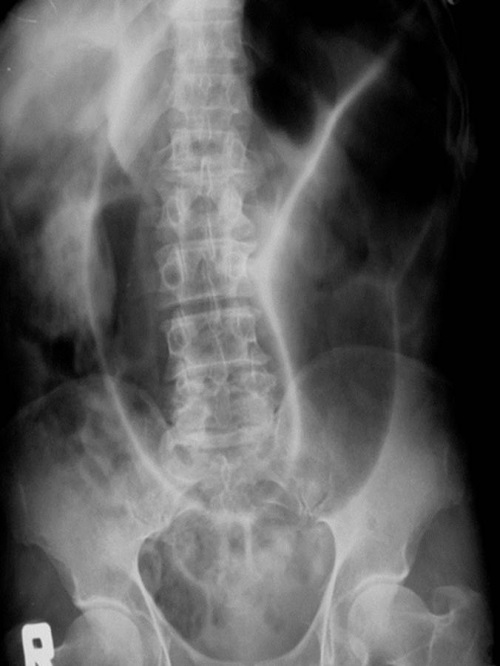

What does this Abdominal polain radiograph show?

Sigmoid volvulus.

Clear “coffee bean sign” and large-bowled obstruction.